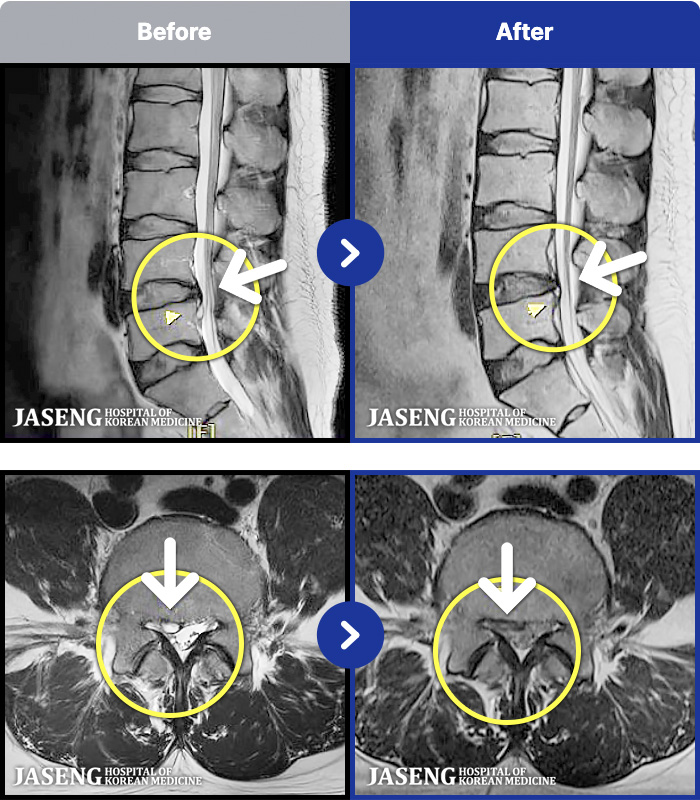

MRI ġ

1,299 MRI ũ ʸ Ȯϼ.